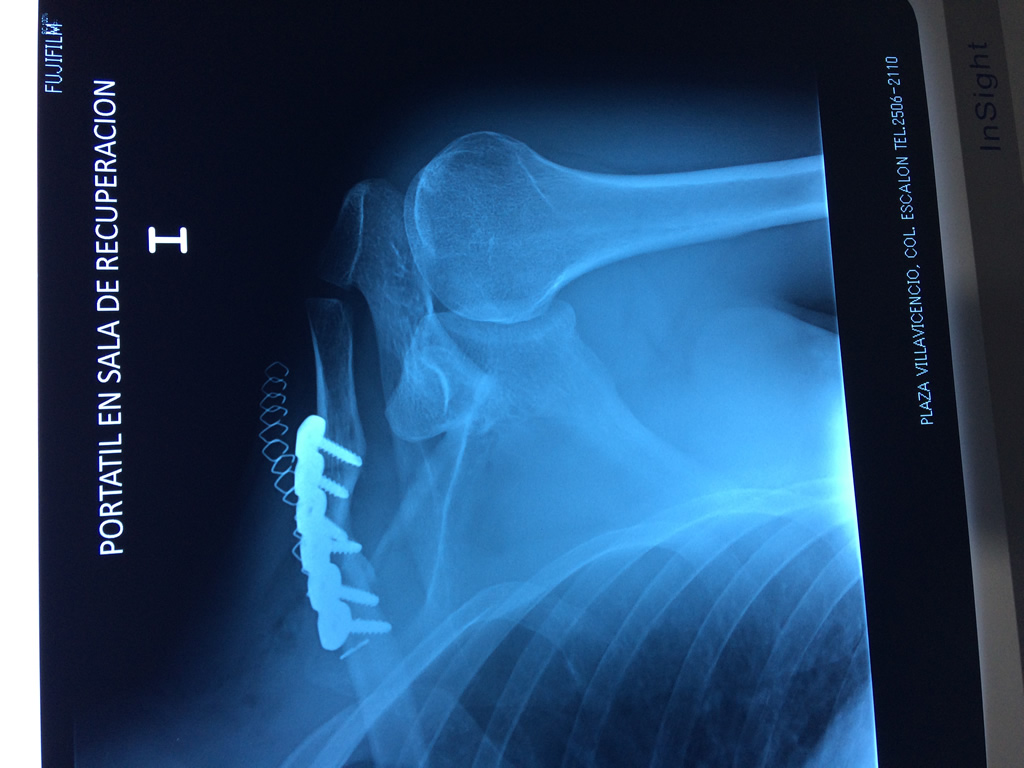

Cirugía de Fémur - Clavícula